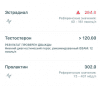

ШикТест энантат PL 125мг 1 раз в 4 дня.

Анализ после 4ой инъекции через 24 часа.

Странная вещь, либидо почему то упало, может эстрадиол взлетел, сдам анализы(обычно по 5 раз в день занимаюсь, а сейчас только 2). Перестал болеть сустав на ноге, раньше вечно ноющие боли, сейчас же вообще не болит, заниматься правда до сих пор не могу боль возвращается. Запрыщавил ппц походу нужен роаккутан, ещё странно что вообще не заливает

Странная вещь, либидо почему то упало, может эстрадиол взлетел, сдам анализы(обычно по 5 раз в день занимаюсь, а сейчас только 2). Перестал болеть сустав на ноге, раньше вечно ноющие боли, сейчас же вообще не болит, заниматься правда до сих пор не могу боль возвращается. Запрыщавил ппц походу нужен роаккутан, ещё странно что вообще не заливает